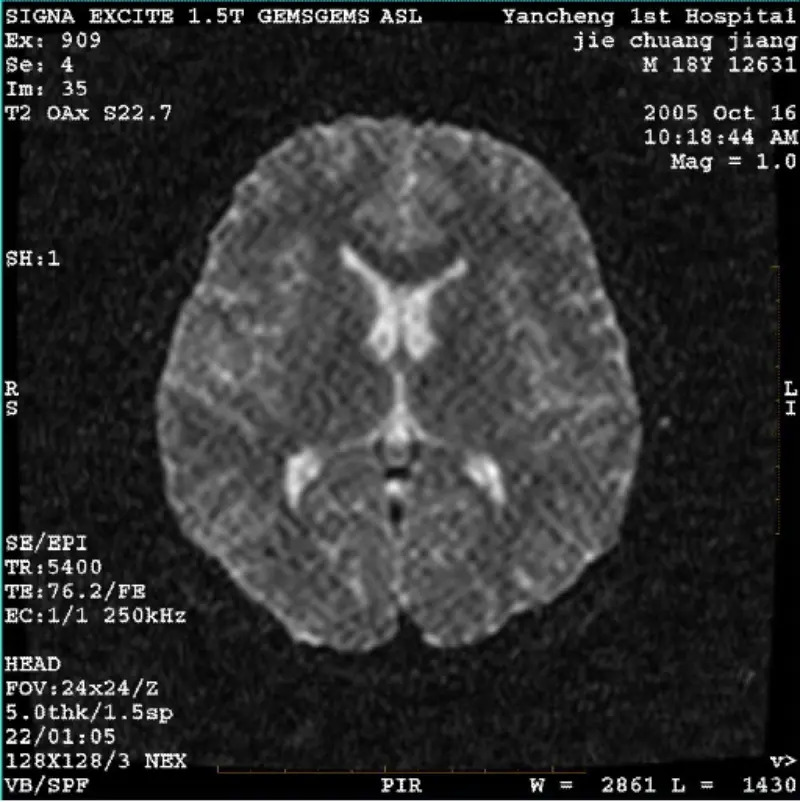

Διαβάστε περισσότεραΣΥΣΤΗΜΑ: 1.5T Signa Twin Excite II (Έκδοση λογισμικού 11.0M4) ΠΡΟΒΛΗΜΑ/ΣΥΜΠΤΩΜΑ DWI (λειτουργία ζουμ και ολόκληρη λειτουργία) και φιέστα (λειτουργία ζουμ και πλήρης λειτουργία) εικόνα που έχει ορατό δικτυωτό ή κοτλέ τεχνούργημα ανεξάρτητα από τη χρήση πηνίου σώματος ή κεφαλής πηνίο, άλλη εικό......